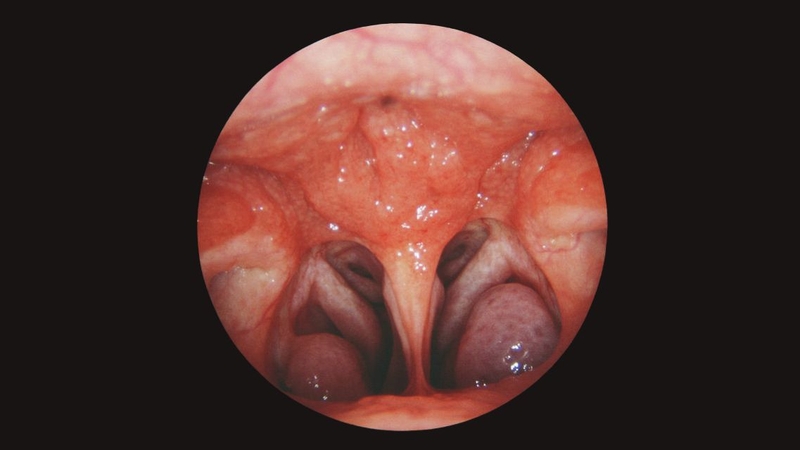

Về mặt giải phẫu, họng gồm 3 phần, mỗi phần nằm ở vị trí khác nhau và thực hiện một chức năng riêng:

Trong vòm họng có các cơ quan miễn dịch quan trọng như amidan vòm và amidan khẩu cái. Chúng có nhiệm vụ nhận diện và chống lại các mầm bệnh xâm nhập vào cơ thể qua đường hô hấp và ăn uống. Hệ thống này đặc biệt đóng vai trò thiết yếu ở trẻ em khi hệ miễn dịch còn non nớt.

Vòng bạch huyết Waldeyer, bao quanh vùng họng, gồm amidan vòm (ở vòm họng), amidan khẩu cái, amidan lưỡi và nhiều nang lympho nhỏ. Trong đó, amidan vòm là phần quan trọng nhất của hệ miễn dịch tại vòm họng. Đây được xem là “lá chắn đầu tiên” của cơ thể, giúp nhận diện và tiêu diệt các tác nhân gây bệnh như vi khuẩn, virus xâm nhập qua đường mũi và miệng. Bên cạnh đó, hệ thống này còn sản sinh tế bào miễn dịch và kháng thể, ngăn không cho mầm bệnh lan sâu vào hệ hô hấp và tiêu hóa, bảo vệ sức khỏe toàn diện cho cơ thể.

Amidan là một phần của hệ miễn dịch, nhưng khi thường xuyên bị viêm nhiễm bởi vi khuẩn hoặc virus, chúng sẽ sưng to, gây đau họng và khó nuốt. Amidan quá phát đặc biệt ảnh hưởng đến ăn uống, giọng nói và chất lượng giấc ngủ, thậm chí có thể gây ngưng thở khi ngủ ở trẻ em và người lớn.